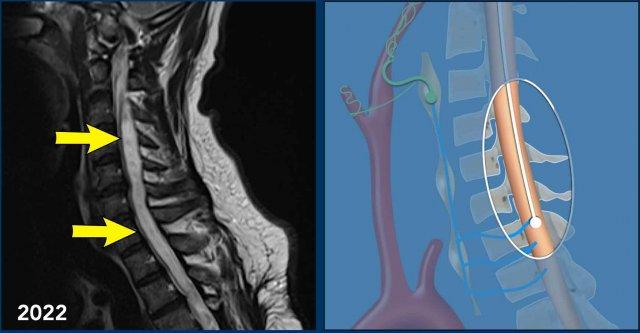

Những hình ảnh này của một người đàn ông 45 tuổi đã bị chấn thương tủy sống do chấn thương ở mức T4-5 vài năm trước.

Hiện tại bệnh nhân có biểu hiện đau tiến triển ở hai chân với giảm phản xạ ở cả hai tay và hai chân cùng với hội chứng Horner hai bên.

Hình ảnh

Hình ảnh cộng hưởng từ cột sống cổ-ngực chuỗi xung T2 TSE theo mặt phẳng đứng dọc năm 2021 cho thấy mất chiều cao thân đốt sống T4 kèm theo tổn thương tủy sống và nhuyễn tủy dạng nang tại vị trí này cùng với hình ảnh rỗng tủy-não thất tủy xung quanh.

Hình ảnh cộng hưởng từ cột sống cổ-ngực chuỗi xung T2W theo mặt phẳng đứng dọc năm 2022 cho thấy hình ảnh rỗng tủy-não thất tủy tiến triển.

Continue with the next images…

Hội chứng Horner có thể được giải thích bởi tình trạng rỗng tủy tiến triển ở mức cổ gây gián đoạn các tế bào thần kinh bậc một của đường dẫn truyền giao cảm nhãn cầu.